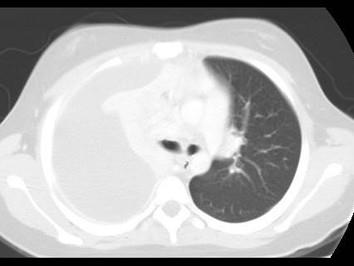

下列图像最佳诊断是什么 ( )A、肺癌B、肺结核C、气胸D、肺不张E、脓胸

选项 A、肺癌 B、肺结核 C、气胸 D、肺不张 E、脓胸

答案 E